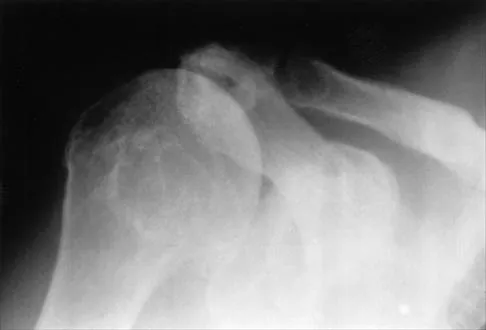

An 11-year-old boy has right shoulder pain and has been unwilling to use the arm after throwing a baseball in a Little League game 3 weeks ago. Examination reveals upper arm and shoulder tenderness with swelling. A radiograph and MRI scan are shown in Figures 27a and 27b. Management should consist of

Explanation

The radiograph is consistent with a unicameral (simple) bone cyst. The MRI scan reveals that the cyst is juxtaposed to the physis and therefore can be classified as active (latent cysts are more than 1 cm away from the physis). Active cysts are treated with aspiration and steroid injection, although repeated injections may be necessary. Curettage and bone grafting results in more reliable healing but may lead to growth arrest in active cysts. Iannotti JP, Williams GR: Disorders of the Shoulder: Diagnosis and Management, ed 1. Philadelphia, PA, Lippincott Williams & Wilkins, 1999, pp 945-946.